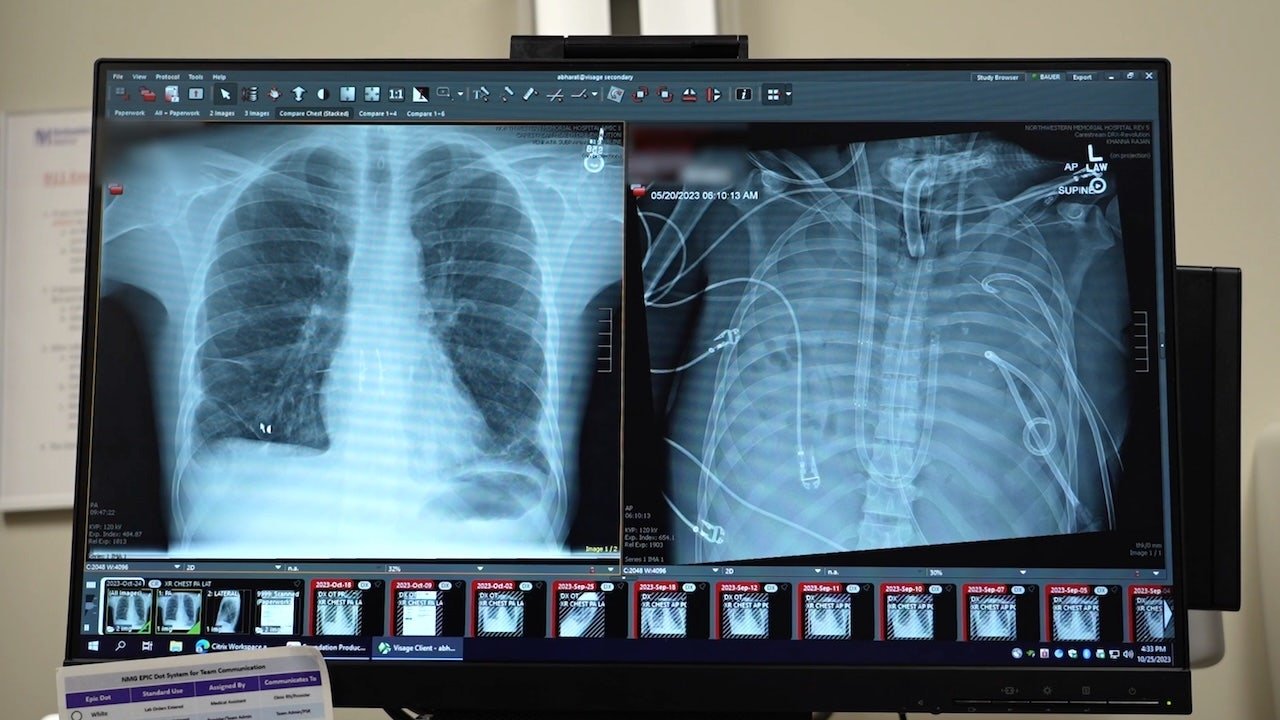

The patient’s new transplant is shown at left, and his old lungs are shown at right. “This technology allows us to ‘clean the slate’ by removing the infection, stabilizing the patient and bridging them to a successful transplant,” the lead surgeon said. (Northwestern Medicine)

“These patients have a mortality rate exceeding 80% and are often turned down for transplant because they are too infected,” Dr. Bharat said. “This technology allows us to ‘clean the slate’ by removing the infection, stabilizing the patient and bridging them to a successful transplant.”